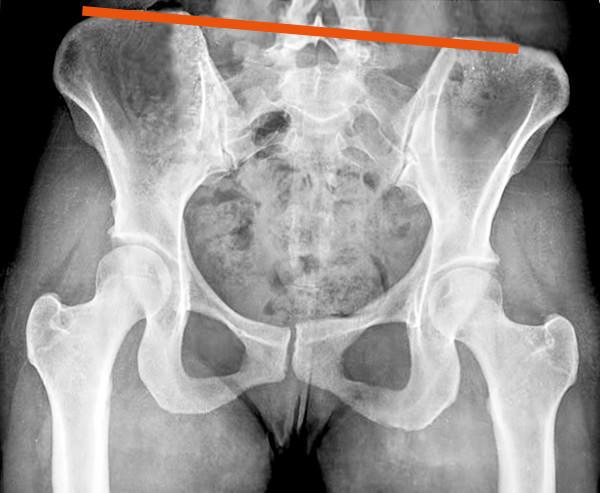

Zur „genauen“ Diagnose einer Beckenschiefstand verlassen sich Ärzte und Orthopäden oft auf eine Röntgenaufnahme des Beckens. Diese Vorgehensweise birgt jedoch einen erheblichen perspektivischen Fehler: Das Becken als dreidimensionale Struktur (Höhe x Breite x Tiefe) wird auf ein zweidimensionales Bild (Höhe x Breite) reduziert.

Diese Einschränkung führt dazu, dass eine Hüfte, die räumlich weiter vorne oder hinten liegt, fälschlicherweise als „höhere Hüfte“ interpretiert wird. Dies kann zu Fehldiagnosen einer vermeintlichen Beinlängendifferenz führen. Experten aus den Bereichen Fotografie und Physik erkennen diesen Fehler sofort.